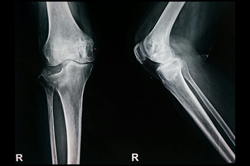

Deformity Correction - Genu Valgum